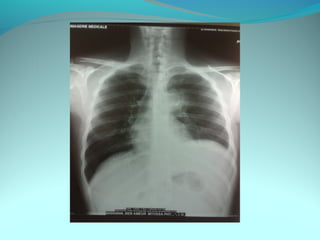

Cliché normal